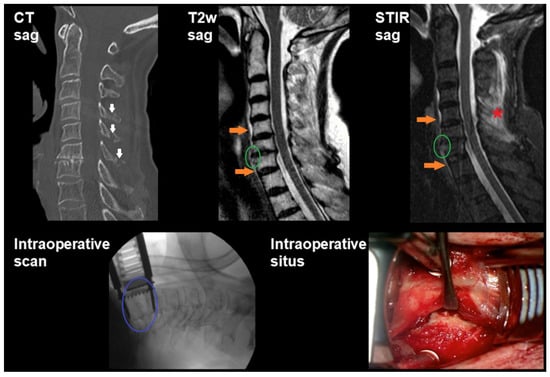

3.2. Imaging and Intraoperative Findings